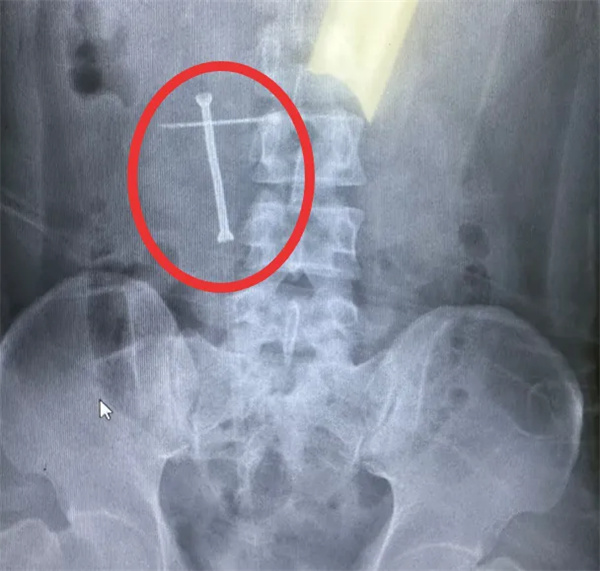

通過術中X線結合輸尿管鏡檢查,醫生精準定位該患者的輸尿管狹窄段長度和位置,利用支架附帶的導入系統精準地將支架放置到預定位置。隨后注入熱水,鎳鈦合金支架雙端膨脹,成功地固定在患者輸尿管狹窄位置,將狹窄段撐開為患者提供尿液引流效果,讓輸尿管狹窄段重新恢復通暢。

(置入支架后,輸尿管狹窄段重新恢復通暢)